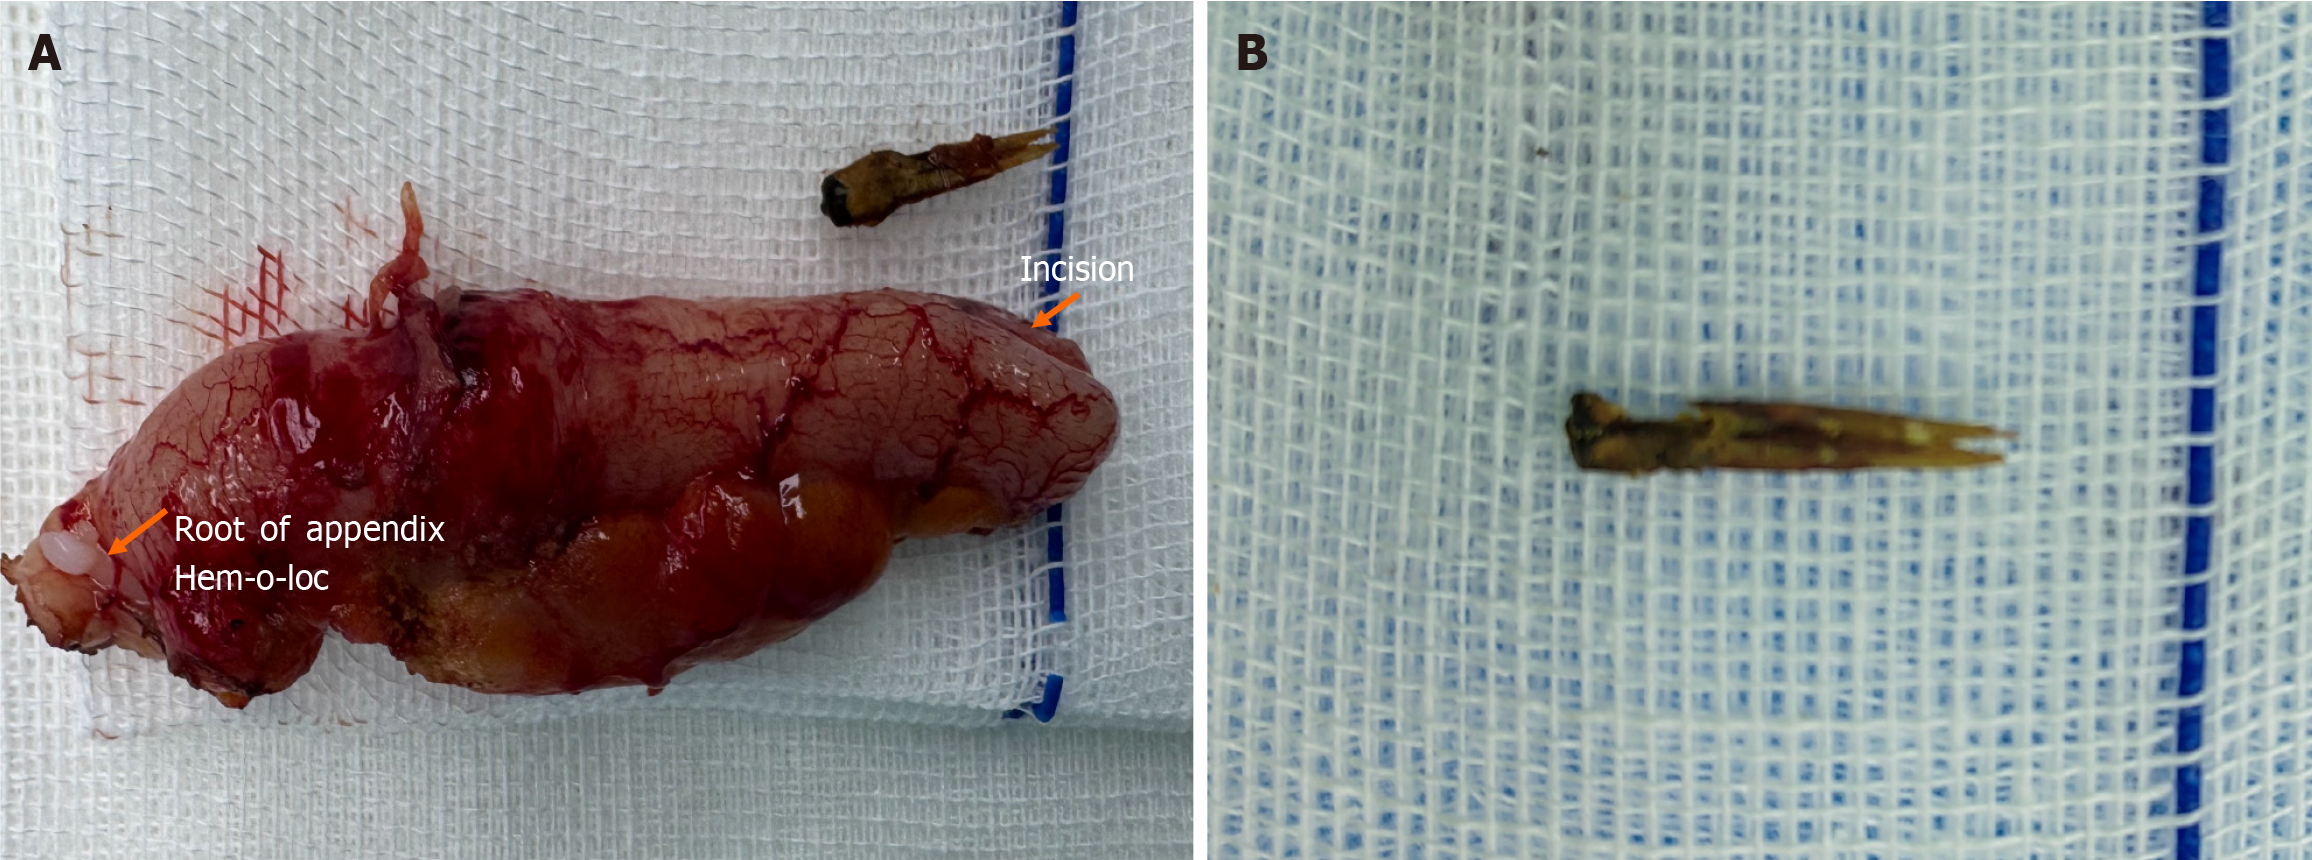

We here report an extremely rare case of chronic appendicitis caused by foreign bodies in the appendix. The patient had a long-term abdominal pain of unclear cause, and she was repeatedly treated in several hospitals. Abdominal color ultrasound examination indicated a coprolith in the appendiceal cavity and the appendix was normal, so the patient could not be treated with surgery. We conducted abdominal computed tomography (CT) examination, and upon the advice of radiologists, we considered the possibility of foreign bodies in the appendix, and excluded other causes of abdominal pain. The patient requested and consented to laparoscopic appendectomy, and a chicken bone was found in the appendiceal cavity by postoperative incision of the appendiceal specimen. The patient recovered and was discharged from hospital. After 2 months of follow-up, abdominal pain did not recur and the patient had a full recovery.

At the request and consent of the patient and her family, laparoscopic appendectomy was performed. During the ope

Chronic appendicitis caused by foreign bodies has not been reported to date. We report an extremely rare case of chronic appendicitis caused by foreign bodies in the appendix. The cause of the patient's long-term abdominal pain was still unclear, and she was repeatedly treated in several hospitals. Abdominal color ultrasound examination indicated that there was coprolith in the appendix, the appendix was normal structurally, and the degree of abdominal pain was mild, so surgery could not be performed. After empirical antibiotic treatment, the patient's abdominal pain was gradually relieved, but abdominal pain often recurs. Other reasons, such as chronic enteritis, chronic pelvic inflammation, etc. which may cause chronic abdominal pain were excluded. Abdominal CT examination revealed a high-density image in the appendiceal cavity. According to radiologists, foreign bodies in the appendix were considered instead of coprolith, and laparoscopic appendectomy was performed upon the request and consent of the patient. Postoperative incision of the appendiceal specimen revealed chicken bones in the appendiceal cavity. The patient recovered and was discharged after surgery. Abdominal pain did not recur during 2 months follow-up. Therefore, it is particularly important that we carefully assess imaging findings and multidisciplinary diagnosis when facing atypical symptoms.